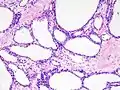

![]() صورة مجهرية تظهر ورم غدي كيسي مصلي في البنكرياس. صبغة الهيماتوكسيلين واليوزين. صورة مجهرية تظهر ورم غدي كيسي مصلي في البنكرياس. صبغة الهيماتوكسيلين واليوزين. | |

صورة مجهرية ورم غدي كيسي مصلي (تكبير متوسط)